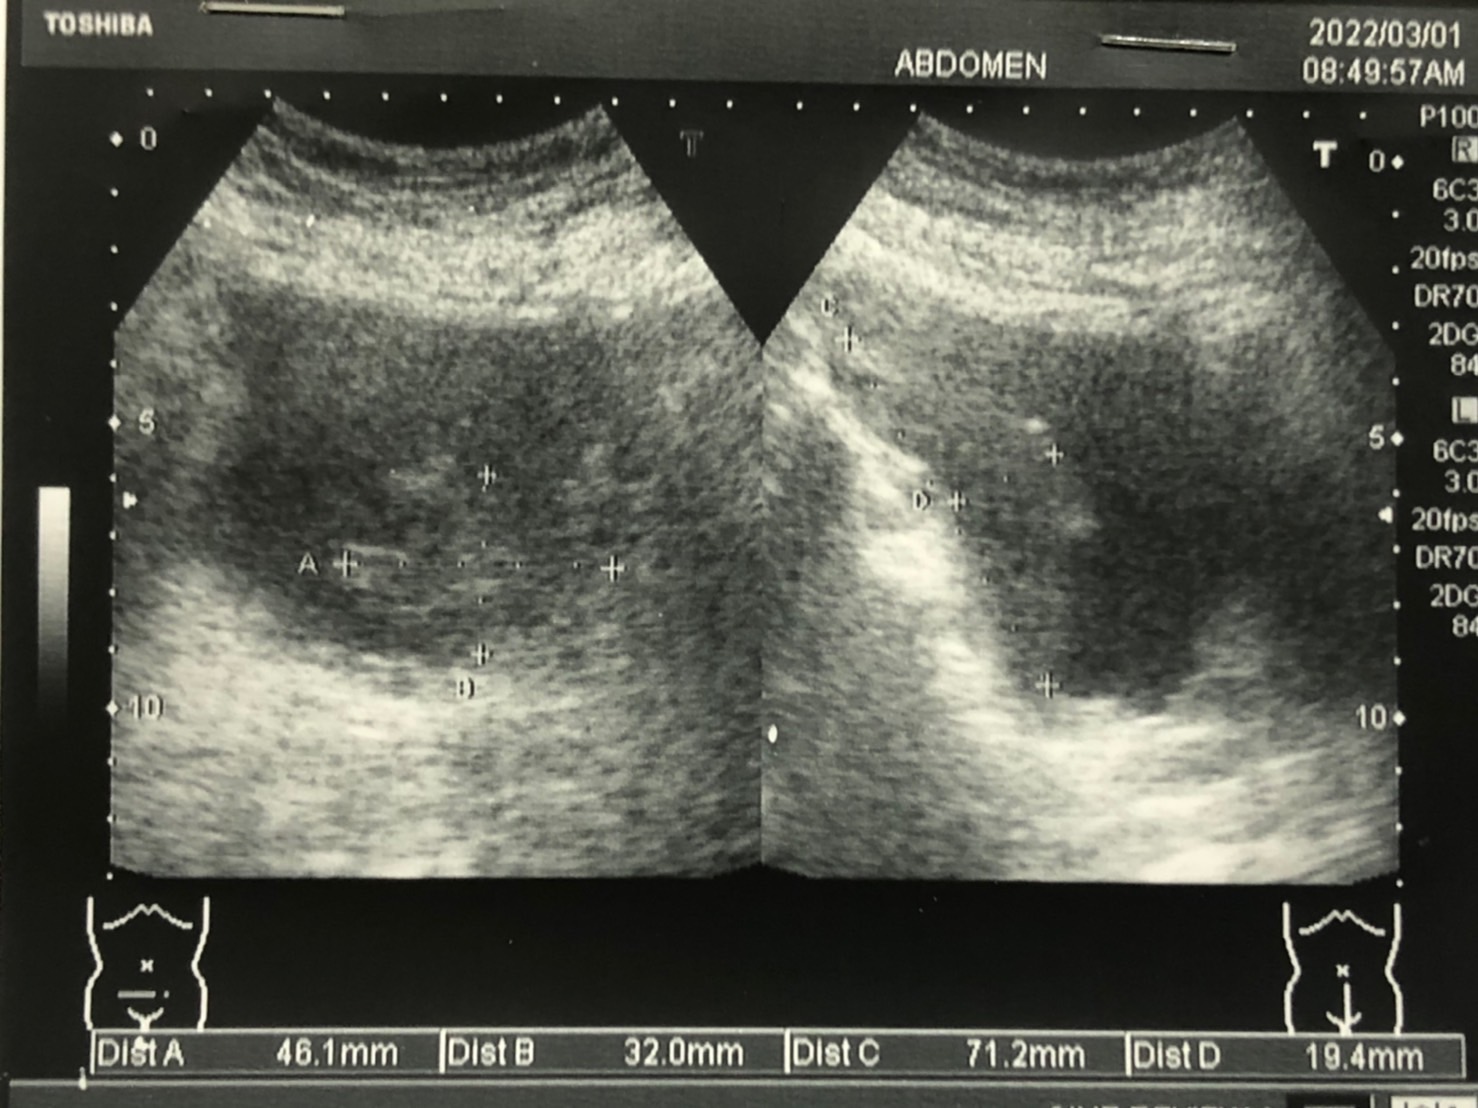

如圖,於超音波下明顯看到了膀胱裡有不規則腫瘤,

當下立即轉診病人至醫院接受進一步評估及治療。

後續,醫院確診為膀胱癌,病患於醫院已接受妥善的治療。